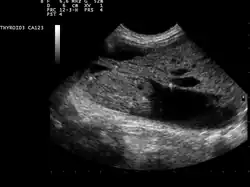

| Ultrasound artifacts showing a "comet tail" from a colloid nodule indicate a benign nodule | |

Ultrasound imaging is useful as the first-line, non-invasive investigation in determining the size, texture, position, and vascularity of a nodule, accessing lymph nodes metastasis in the neck, and for guiding fine needle aspiration cytology (FNAC) or biopsy. Ultrasonographic findings will also guide the indication to biopsy and the long term follow-up.[10] High frequency transducer (7–12 MHz) is used to scan the thyroid nodule, while taking cross-sectional and longitudinal sections during scan. Suspicious findings in a nodule are hypoechoic, ill-defined margins, absence of peripheral halo or irregular margin, fine, punctate microcalcifications, presence of solid nodule, high levels of irregular blood flow within the nodule[11] or "taller-than-wide sign" (anterior-posterior diameter is greater than transverse diameter of a nodule). Features of benign lesion are: hyperechoic, having coarse, dysmorphic or curvilinear calcifications, comet tail artifact (reflection of a highly calcified object), absence of blood flow in the nodule, and presence of cystic (fluid-filled) nodule. However, the presence of solitary or multiple nodules is not a good predictor of malignancy. Malignancy is only diagnosed when ultrasound findings and FNAC report are suggestive of malignancy.[11] The TI-RADS (Thyroid Imaging Reporting and Data Systems) are sonographic classification systems which describe the suspicious findings of thyroid nodules.[12] It was first proposed by Horvath et al.,[13] based on the BI-RADS (Breast Imaging Reporting and Data System) concept. Several systems were subsequently proposed and adopted by international scientific societies. Their main aims are to characterize the risk of malignancy of nodules to better select nodules to submit to fine-needle aspiration cytology.[14] TI-RADS developed by the American College of Radiology (ACR) guides clinicians in deciding which nodules require FNAC and in planning follow-up. Various online tools have been developed to assist in applying these criteria to clinical practice. [15]